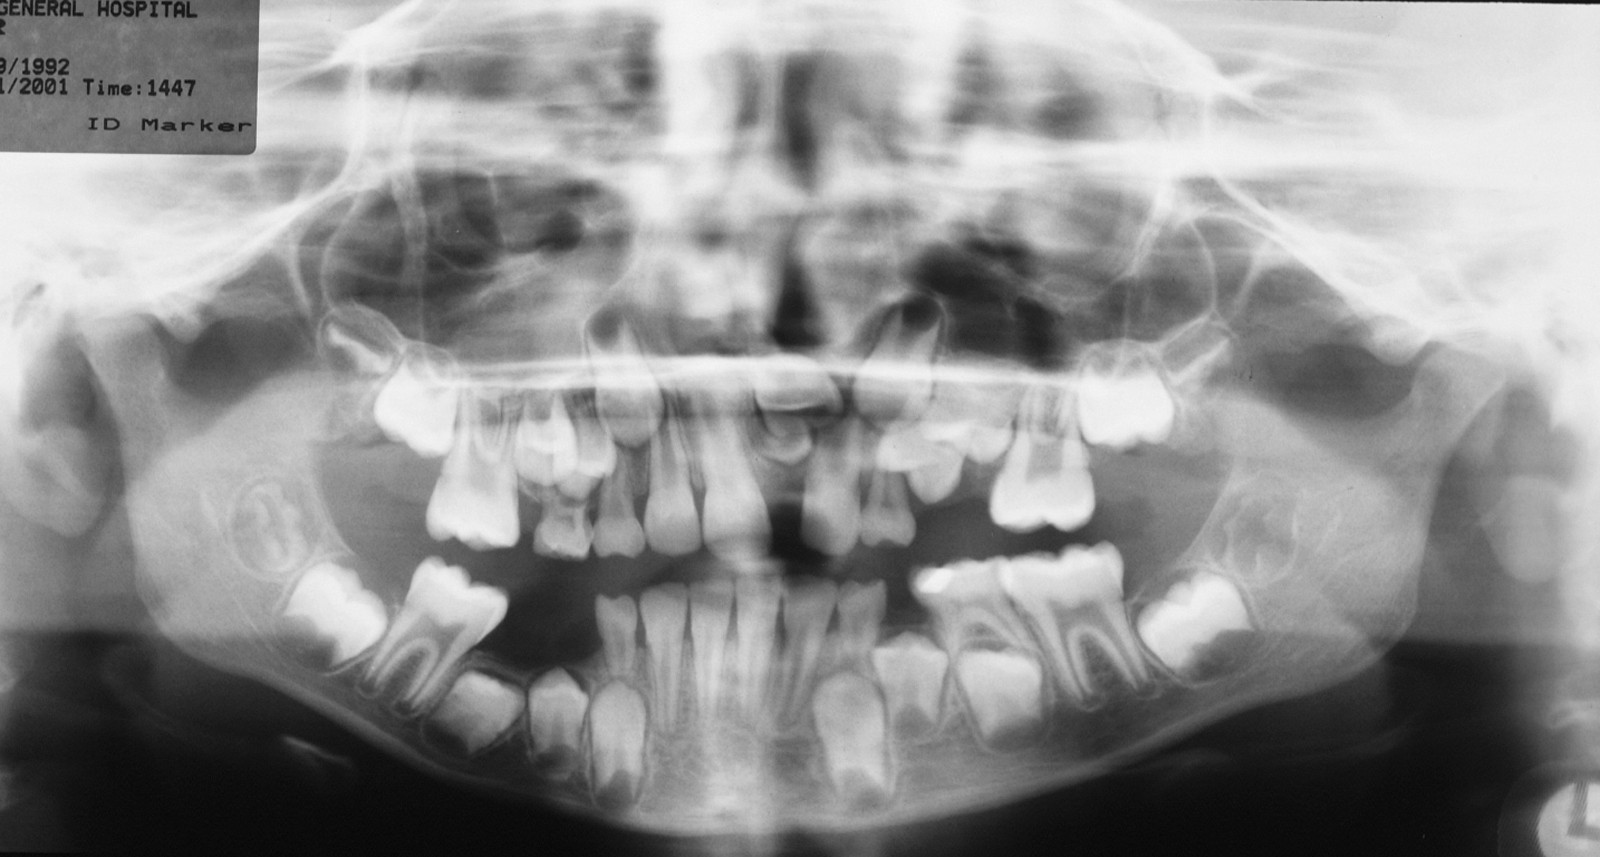

Figure 2 and Figure 3 illustrate examples of indications for removal of a third molar tooth.

Assessment of the tooth is both clinical and radiographic. If somebody presents in pain, it is important to establish that this is coming from the third molar and not elsewhere. Pain is often vague, poorly localised and may be referred from another tooth, or as part of facial arthromyalgia (condition affecting the jaw joint). A dental panoramic radiograph is ideal as it helps to assess all the teeth at once. The health of the adjacent molars may influence the decision whether to remove the third molar or not. Large crowns or old restorations are all at risk of dislodgement during surgery. It is also worth considering whether alternative treatment options are available. For instance, pericoronitis due to an over-erupted upper third molar may be dealt with by extracting that tooth only, with or without operculectomy. In the presence of other teeth of poor prognosis, will it be better in the long term to save the third molar which may be used as a denture or bridge abutment in the future?

These points help to determine whether the tooth can be simply elevated or will need a surgical approach. A series of radiographs depicted in Figure 4 to Figure 8 illustrate these points further.